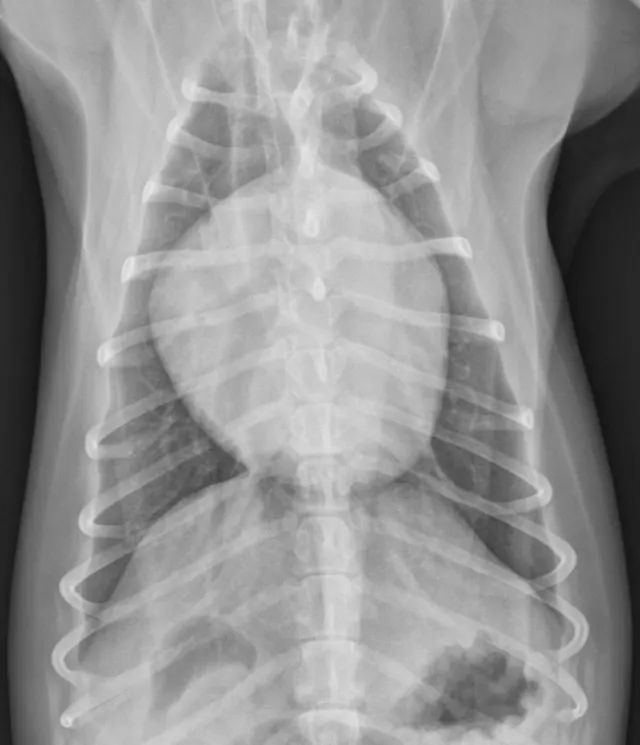

Right lateral (Figures 1 and 2) and dorsoventral (Figures 3 and 4) radiographs of 2 dogs with grade 3/6, holosystolic, left apical murmurs. Dog 1 (Figures 1 and 3) has mild left atrial enlargement; dog 2 (Figures 2 and 4) has a severely enlarged left atrium.